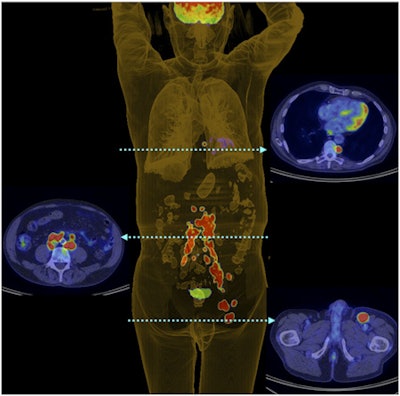

Winner: 3D PET digital reconstruction of Merkel cell carcinoma patient

A new category in the Minnies this year, the Best Radiology Image award goes to a PET scan of a patient with Merkel cell carcinoma, an aggressive skin disease that often reoccurs and carries a high risk of both nodal and distant metastases.

Researchers from Peter MacCallum Cancer Centre and the University of Melbourne acquired the image as part of a clinical study on the effectiveness of F-18 FDG PET in patients with Merkel cell carcinoma. They wanted to see how well PET could be used to stratify patients with the disease, which, while rare, nearly tripled in incidence in the U.S. between 1986 and 2001. Their results were published in the August 2013 issue of the Journal of Nuclear Medicine.

Surgical resection is typically the most common treatment for Merkel cell carcinoma, but it has a high rate of locoregional failure if not followed by postoperative radiation therapy. PET has been used in small studies with promising results in improving patient management, so the group wanted to investigate in a larger population whether the modality could stratify patients and predict their prognosis.

In the study, 102 patients were staged using PET, and the researchers examined whether the scans resulted in a change in patient management. They found that the imaging technique did, in fact, change treatment for 38 patients, and PET altered staging for 22 patients.

The scan named as Best Radiology Image is a 3D digital PET reconstruction that shows left inguinal nodal and extensive retroperitoneal and thoracic nodal metastases in a patient with left-lower-limb Merkel cell carcinoma.